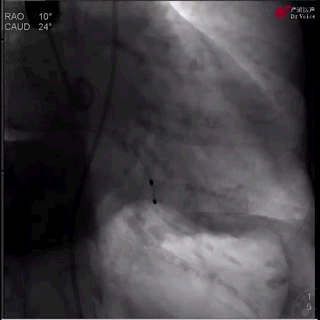

2、导丝顺利跨瓣后,在无冠窦猪尾指示下,将装载瓣膜的输送系统送至窦底;

瓣膜输送并跨瓣(过弓中)

3、对于主动脉瓣反流患者,冠状窦底比主动脉瓣环位置略低,因此彭小平教授将输送系统向更高位置做细微调整,造影明确定位;

瓣膜定位